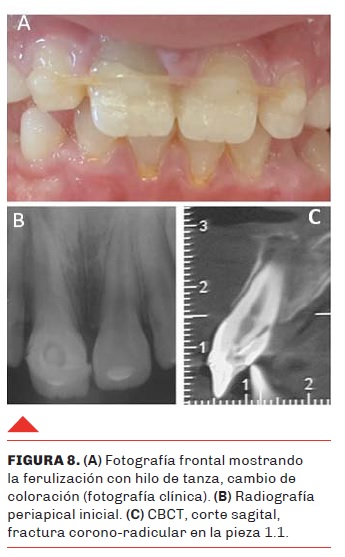

Al momento del examen clínico se observó: ferulización con hilo de tanza que involucraba las piezas 1.2, 1.1, 2.1 y 2.2, cambio de coloración y apertura endodóntica comunicada al medio bucal en 1.1 (Figura 8 A). En la radiografía periapical se evidenció formación radicular completa, radiolucidez apical y una línea de fractura no precisa en el 1.1, por lo cual se solicitó una tomografía computarizada de haz cónico (CBCT) en cortes de 1 mm, que confirmó la existencia de fractura corono-radicular (Figura 8 B y C). En la consulta de urgencia se realizó el tratamiento endodóntico obturando mediante la técnica de condensación lateral con conos de gutapercha y sellador endodóntico y se cementó un poste de fibra de vidrio con el objetivo de unir los cabos de fractura para mantener la misma corona dentaria adherida y luego retirar la férula (Figura 9 A, B y C).